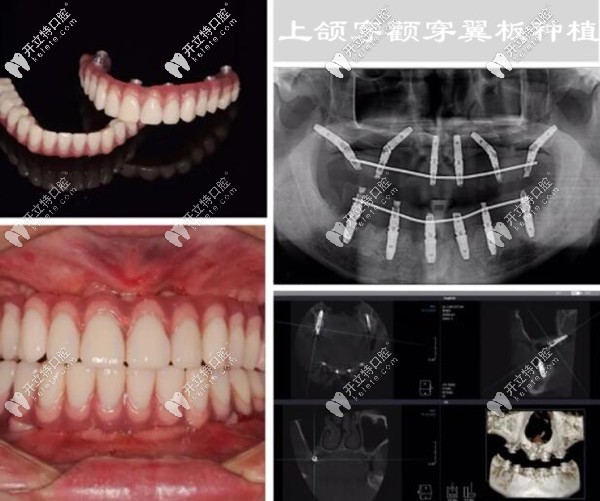

沒有對(duì)比就沒有傷害,下面是我做全口種植牙前后的照片,誰能想到這是同一個(gè)人▼

深圳登緹斯口腔的醫(yī)生考慮到我對(duì)傳統(tǒng)種植牙技術(shù)的擔(dān)憂,就對(duì)我的牙槽骨情況做了詳細(xì)分析,建議上頜采用雙側(cè)穿顴穿翼板種植、即刻修復(fù)即刻負(fù)重技術(shù),不用植骨、縮短療程;下頜采用即拔即種的即刻負(fù)重種植技術(shù)。

其實(shí),手術(shù)前我很緊張、也很擔(dān)心,怕手術(shù)有風(fēng)險(xiǎn)~~~~在登緹斯口腔的種植醫(yī)生團(tuán)隊(duì)的配合下,做了術(shù)前的仔細(xì)、周密準(zhǔn)備,從拔殘牙根開始,用了兩個(gè)多小時(shí);手術(shù)挺順利、術(shù)后就戴了臨時(shí)牙冠,從術(shù)后的CT片上能看出每顆種植體的位置都很精準(zhǔn)。